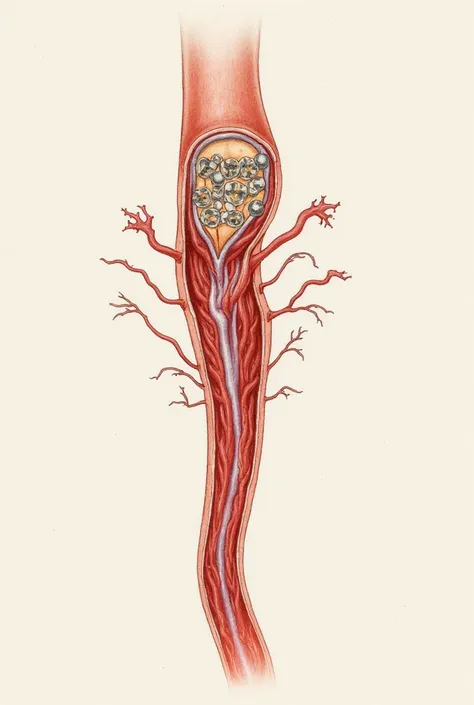

A diagram of the anatomy of the human body